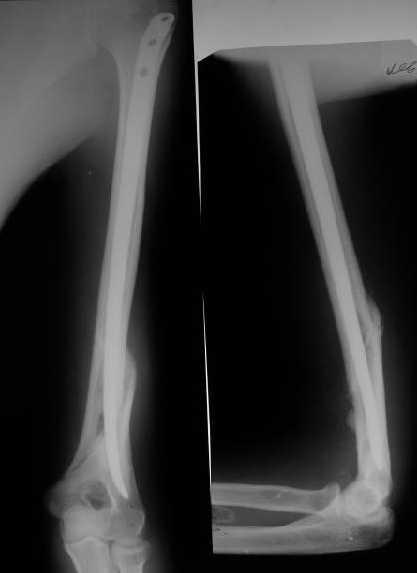

Мы в последние годы все еще используем для переломов такой локализации эластичные титановые стержни (по мотивам ярославских разработок, Зверева-Ключевского). Такой стержень можно вводить не через сухожилие надостной мышцы, а дистальнее.

Снимки до, через 1 и 2 мес. после синтеза.